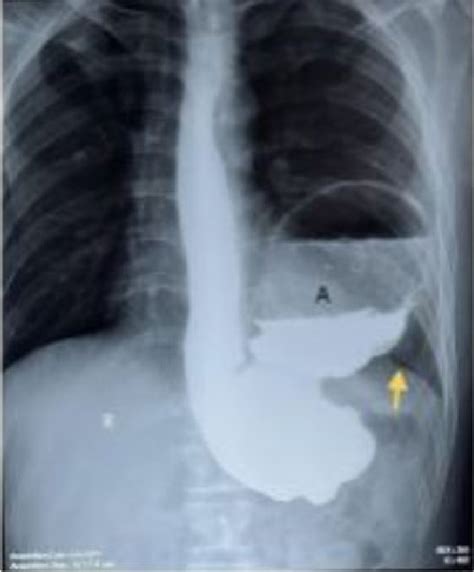

When you experience persistent digestive issues such as difficulty swallowing, chronic heartburn, or unexplained abdominal pain, your healthcare provider may recommend diagnostic imaging to get a clearer picture of what is happening inside your body. One of the most common and effective tools used for this purpose is the Upper GI Series. This procedure is a safe and non-invasive way to examine the upper gastrointestinal tract, which includes the esophagus, stomach, and the first part of the small intestine, known as the duodenum. By using a special form of X-ray called fluoroscopy and a contrast material called barium, doctors can visualize the structure and function of these organs in real-time, helping them identify abnormalities that might not be visible on standard X-rays.

The Upper GI Series, sometimes referred to as a barium swallow or a barium meal, is a fluoroscopic examination. Unlike a static X-ray, fluoroscopy acts like a movie, allowing radiologists to observe the movement of the contrast agent as it passes through your digestive system. This dynamic view is crucial for identifying issues related to how the muscles in your esophagus and stomach are functioning, not just what the organs look like structurally.

The contrast material, a chalky white liquid containing barium, coats the lining of the esophagus, stomach, and duodenum. Because barium is a radio-opaque substance, it shows up brightly on X-ray images, providing a sharp outline of the organ walls. This makes it much easier for medical professionals to detect conditions such as ulcers, tumors, inflammation, or structural irregularities.